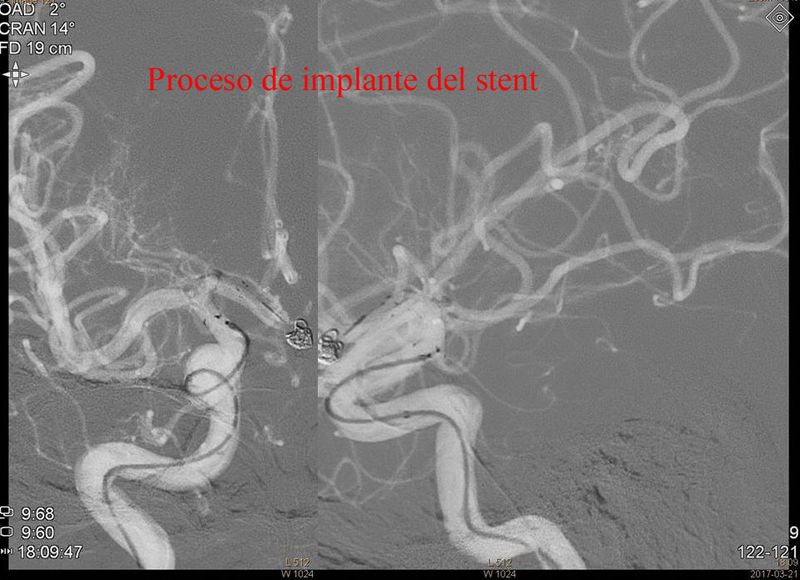

Aneurisma de cara posterior de A1